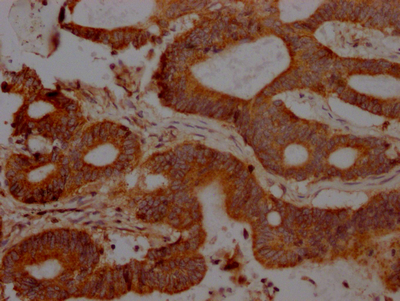

IHC image of CSB-RA252392A0HU diluted at 1:100 and staining in paraffin-embedded human colon cancer performed on a Leica BondTM system. After dewaxing and hydration, antigen retrieval was mediated by high pressure in a citrate buffer (pH 6.0). Section was blocked with 10% normal goat serum 30min at RT. Then primary antibody (1% BSA) was incubated at 4℃ overnight. The primary is detected by a Goat anti-rabbit IgG polymer labeled by HRP and visualized using 0.05% DAB.